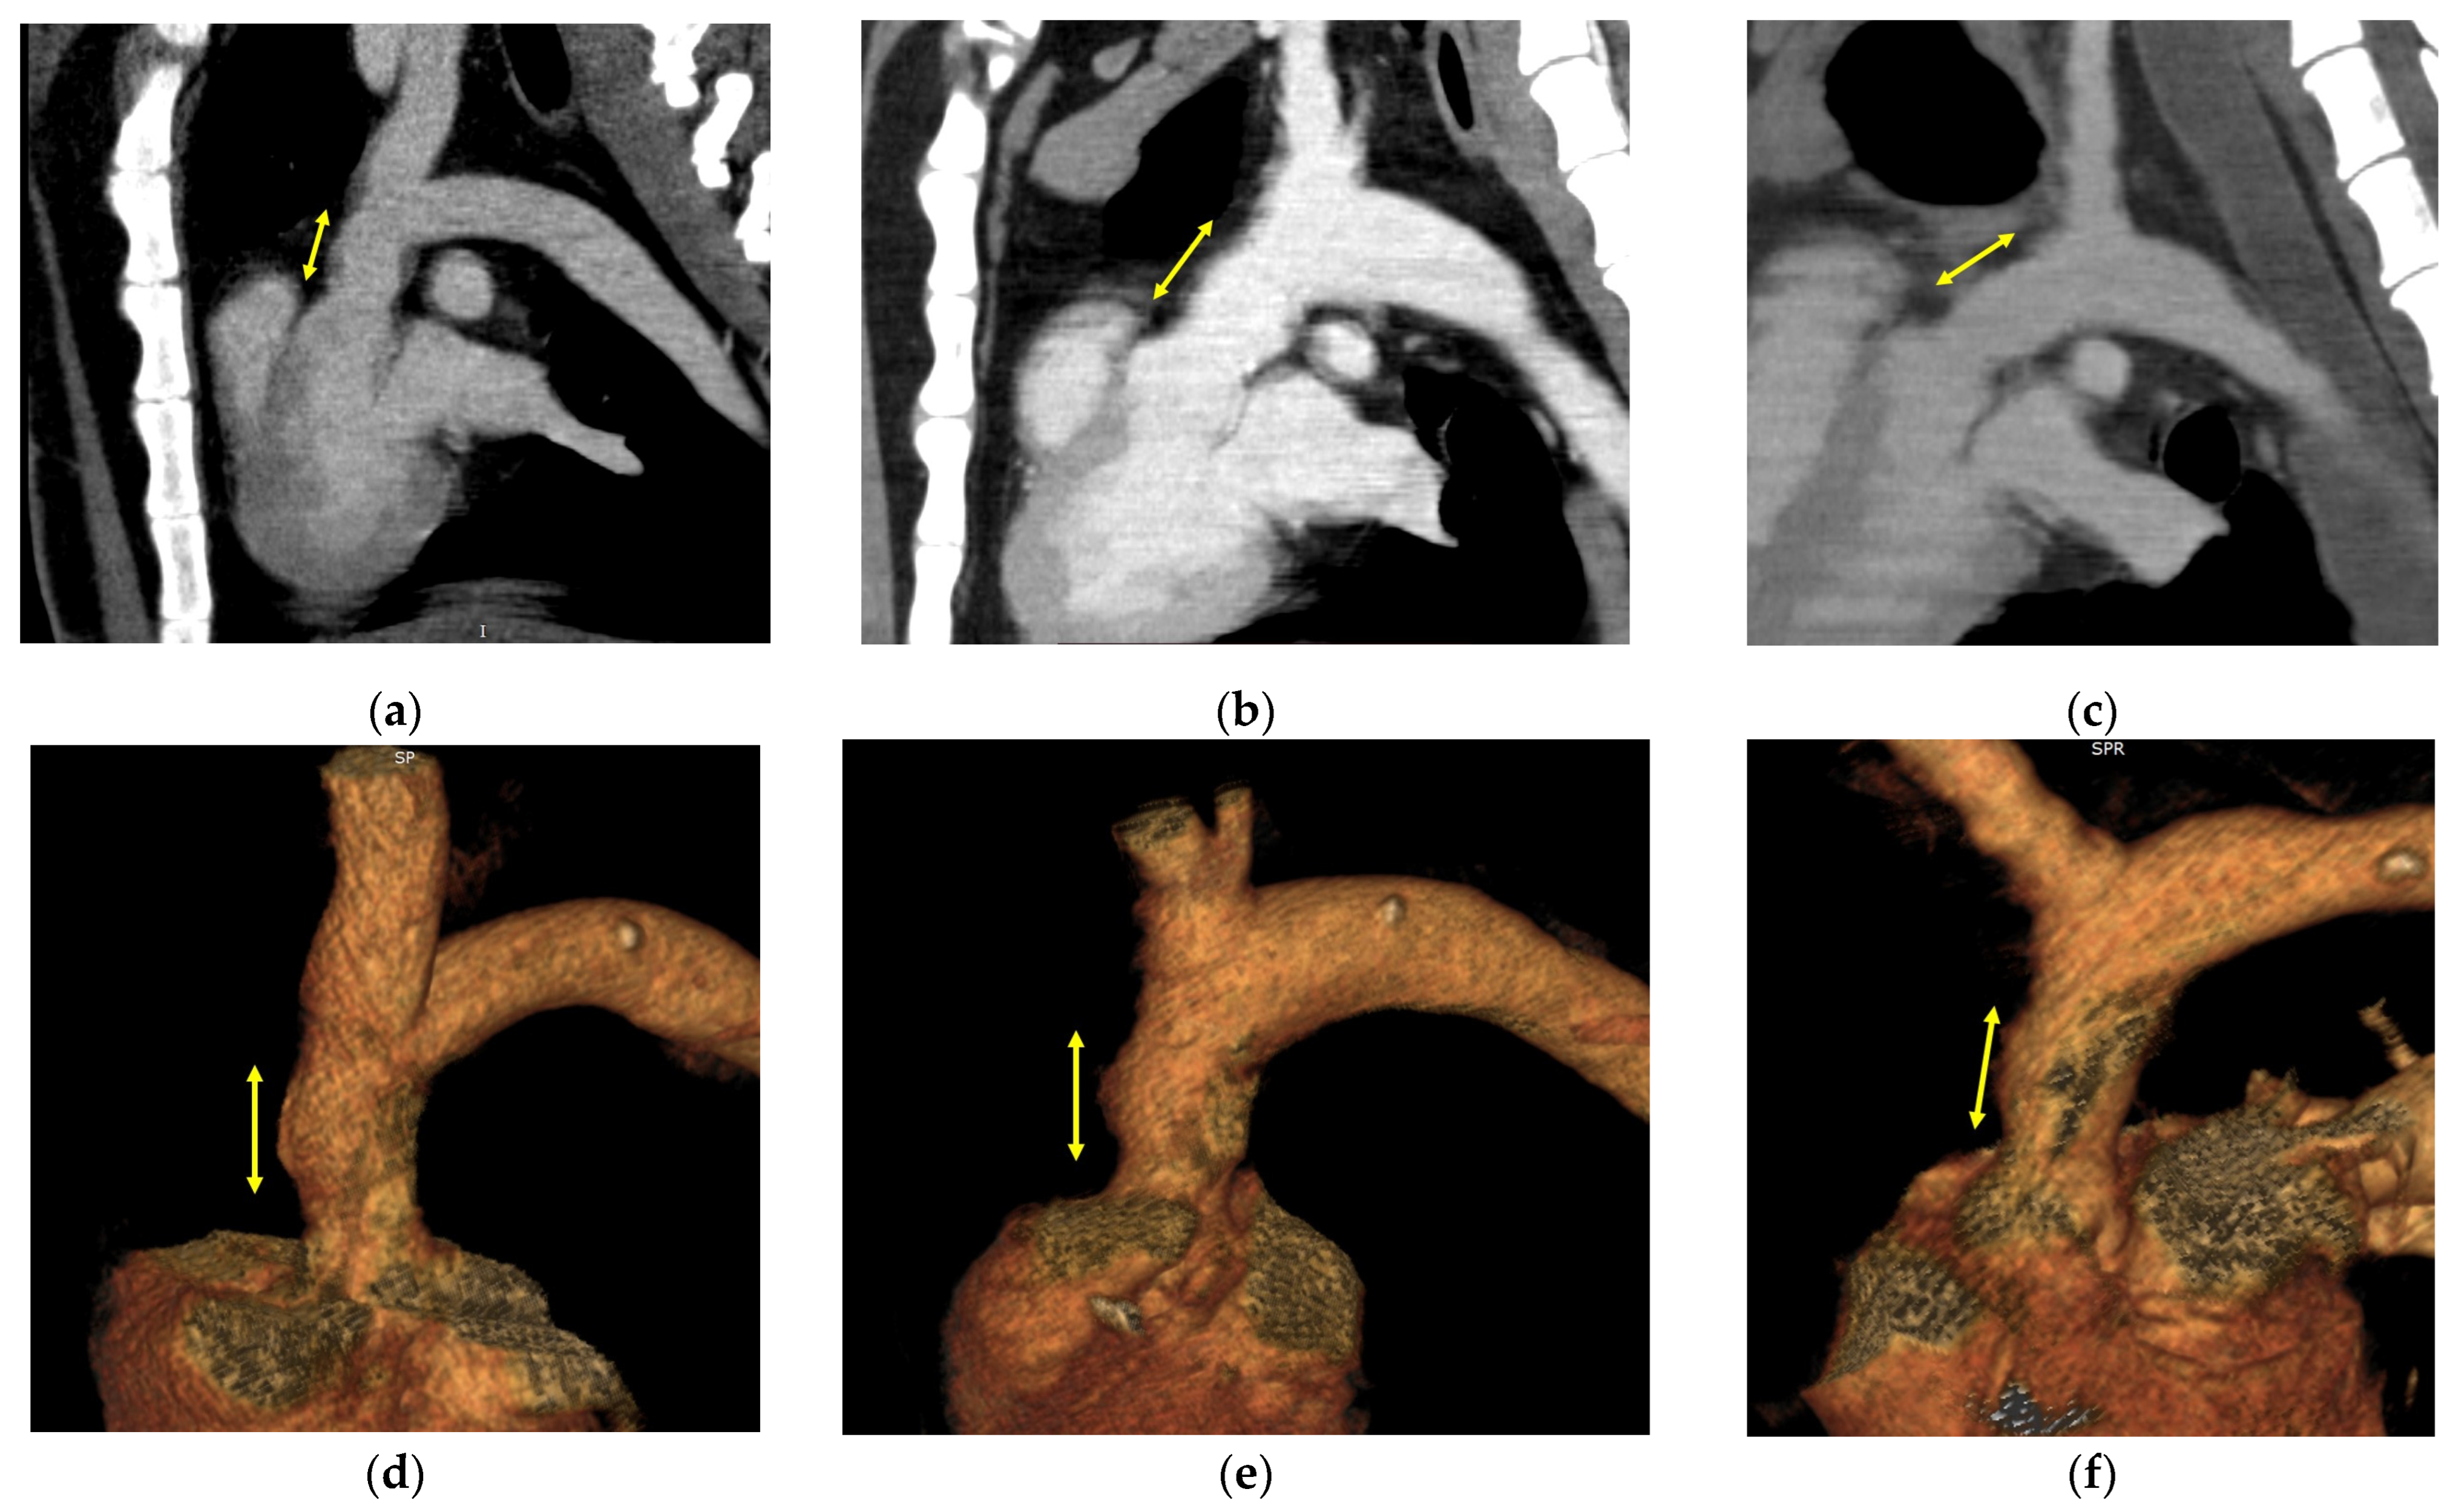

3.2. Image Evaluation